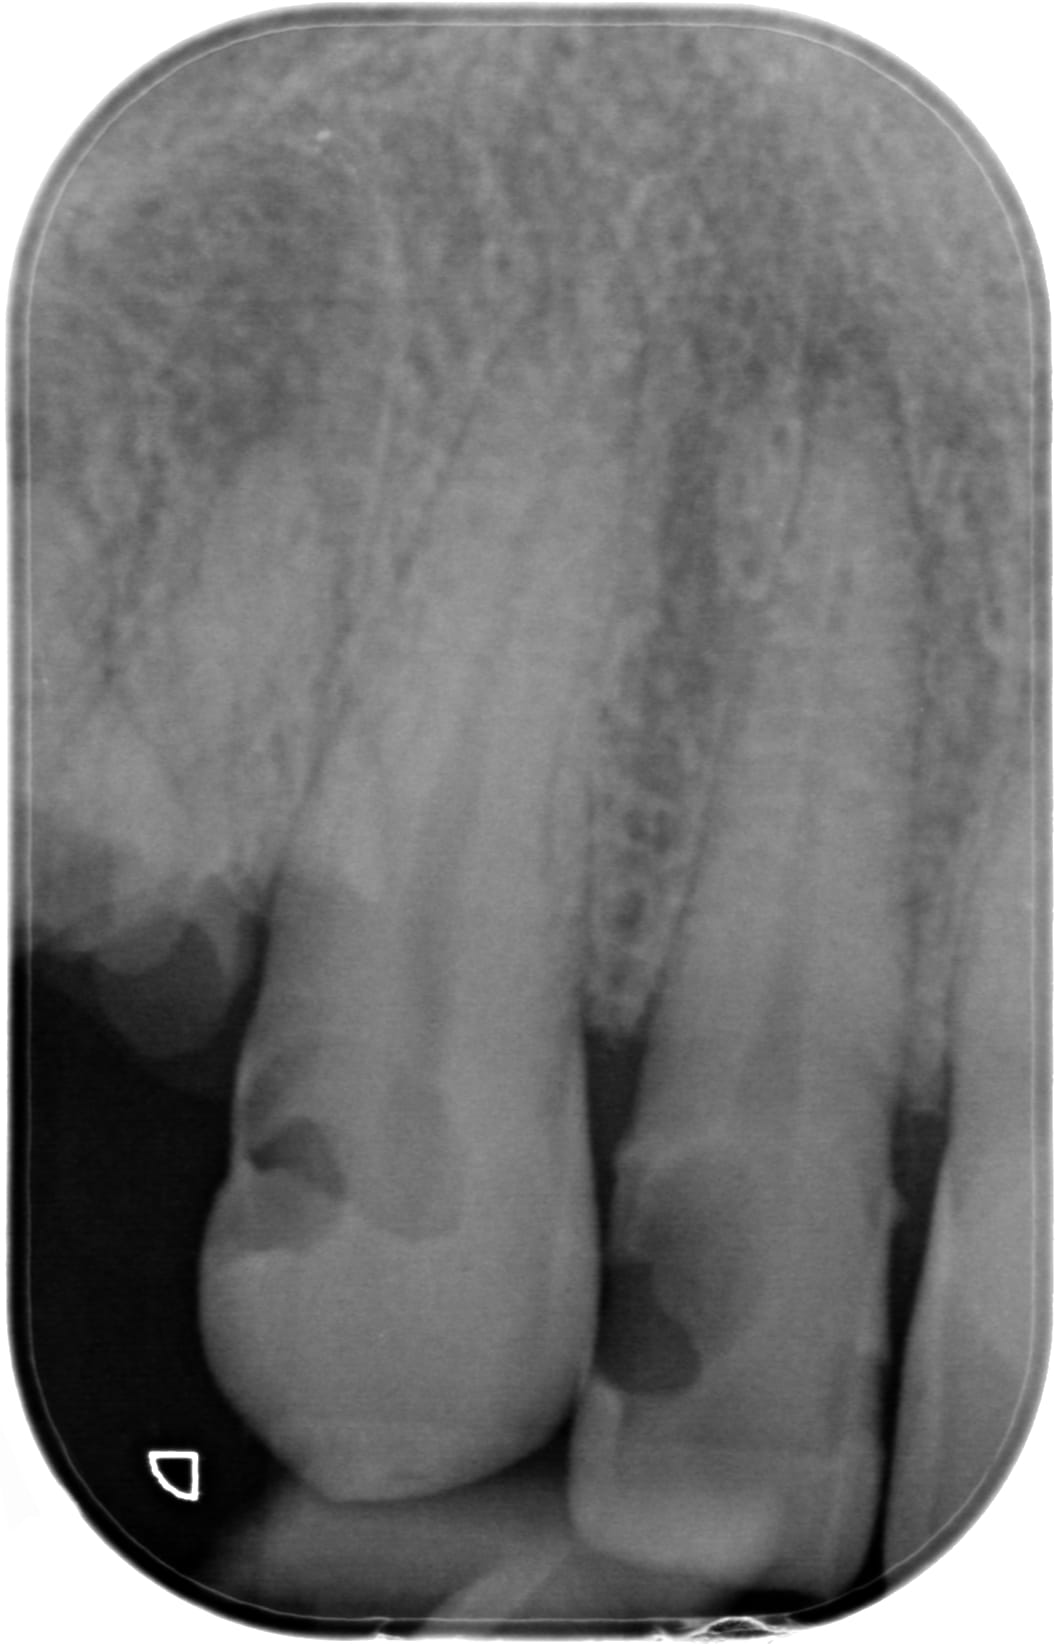

Des comme ça j'en 2 ou 3 par semaine (vu à l'instant ) ... Petite question : quel âge à ce patient ? Deuxième question à Carident et à quelques autres, quel est le montant de votre plan de traitement ? ( je ne demande pas le détail )(@ lardon , la 15 en métal , marqueur social ? ) .. troisième question : pensez vous que ce patient a la mutuelle adéquate à son état dentaire et enfin : pensez-vous que ce patient serait mieux pris en charge grâce au RAC 0 ? On va faire dans le concret de pas mal de cabinet dentaire ....

Pour l'age, c'est pas pour l'expulser, mais c'est impossible à dire par rapport à la radio. Au delà de 18 ans, c'est certain, tu ne sera pas arrêté pour détournement de mineur.

Puisque tu en parles, ca doit être la trentaine. Il a eut différentes extractions réalisées au cour du temps et à abandonné déjà les soins en cours de route.

C'est bien pour cela que c'est impossible de parler de devis et de tarifs, puisque quelque soit le devis, les probabilités d'arriver au bout du plan de traitement sont faible et il abandonnera bien avant les prothèses sur des soins opposables ce qui montre que le tarif et les remboursements ne sont pas en cause.

26/02/2018 à 12h12

Age 19 Ans ! , et bien sûr qu'il ira au bout du traitement s' il peut financièrement ! Il est motivé , c'est un jeune homme "bien" . sérieux , il est à l'heure , n'est pas peureux .. bref , ce genre de patient où tu sais pertinemment que ce qui va coincer c'est l'argent . Barba , il existe des patients non serieux à tous les niveaux de la société et quand c'est un cadre , là , on pense qu'il n'a pas le temps . Alors , on fait quoi pour ce jeune , on le prend en charge ( nous la société ...) ? on lui dit que c'est trop tard ? t'avais qu'à te brosser les dents ? ( vous avez remarqué qu'il a eu déjà de nombreux soins ) . Et, s'il vous plait, gardez pour vous vos généralisations à 2 balles ! ( barba , tu me suis ? ) . Ah ouais aussi , je ne lui ai pas mis un devis sous le nez avant de commencer à le soigner .. évidemment !

Je précise aussi , ce patient n'est pas venu parce qu'il avait mal .... étrange , non ?